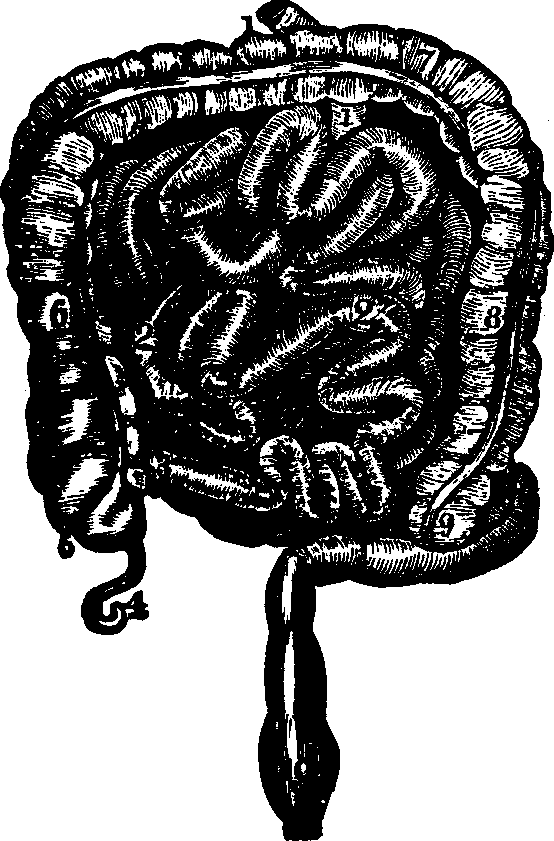

Fig. 29. Small and large intestines. 1, 1, 2, 2. Small intestine.

3. Its termination in the large intestine. 4. Appendix

vermiformis. 5. Cæcum. 6. Ascending colon. 7.

Transverse colon. 8. Descending colon. 9. Sigmoid flexure of

colon. 10. Rectum.

The Intestines are those convoluted portions of the alimentary

canal into which the food is received after being partially digested, and

in which the separation and absorption of the nutritive materials and the

removal of the residue take place. The coats of the intestines are

analogous to those of the stomach, and are, in fact, only extensions of

them. For convenience of description, the intestines may be divided into

the small and the large. The small intestine is from twenty

to twenty-five feet in length, and consists of the Duodenum, Jejunum, and

Ileum. The Duodenum, so called because its length is equal to the

breadth of twelve fingers, is the first division of the small intestine. If

the mucous membrane of the duodenum be examined, it will be found thrown

into numerous folds, which are called valvulæ conniventes, the

chief function of which appears to be to retard the course of the

alimentary matter, and afford a larger surface for the accommodation of the

absorbent vessels. Numerous villi, minute thread-like projections,

large intestine is about five feet in length, and is divided into the

Cæcum, Colon, and Rectum. The Cæcum is about three inches in

length. Between the large and the small intestine is a valve, which

prevents the return of excrementitious matter that has passed into the

large intestine. There is attached to the cæcum an appendage about

the size of a goose-quill, and three inches in length, termed the

appendix vermiformis. The Colon is that part of the large

intestine which extends from the cæcum to the rectum, and which is

divided into three parts, distinguished as the ascending, the transverse,

and the descending.